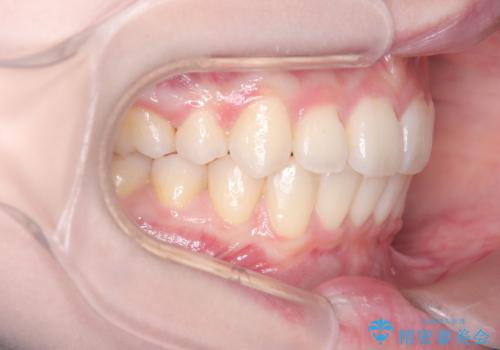

特に下顎の右方偏位に対しては、ワイヤーによる繊細なコントロールを行い、左右の咬合バランスを整えることに重点を置きました。2年半の治療期間を経て、突出していた前歯は理想的な位置に収まり、顎のズレも大幅に改善されました。

治療完了後は、お顔全体のバランスが整い、横顔のライン(Eライン)も美しく変化しました。審美ワイヤーを使用したことで、長期間の治療中もストレスを最小限に抑えながら、機能的で健康的な咬み合わせを獲得することができました。